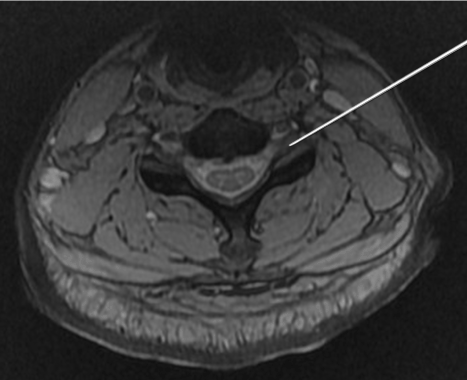

Findings on magnetic resonance imaging would include a subdural fluid collection, the MR signal characteristics of which depend on the age of the hematoma (Figures 7a, 7b, 7c). Acute hematoma which contains deoxyhemoglobin is iso- to hypointense on T1-weighted images and hypointense on T2-weighted images. Intracellular methemoglobin within early subacute hematoma is T1 hyperintense and T2 hypointense while extracellular methemoglobin within late subacute hematoma is hyperintense on both T1- and T2-weighted images.

Figure 7. (a)Sagittal T1 and (b) T2-weighted images of the lumbosacral spine show a late subacute subdural hematoma extending from the inferior border of the T12 vertebra to the level of S2. (c)Axial T1-weighted image again shows the late subacute haematoma within the lumbosacral spinal canal